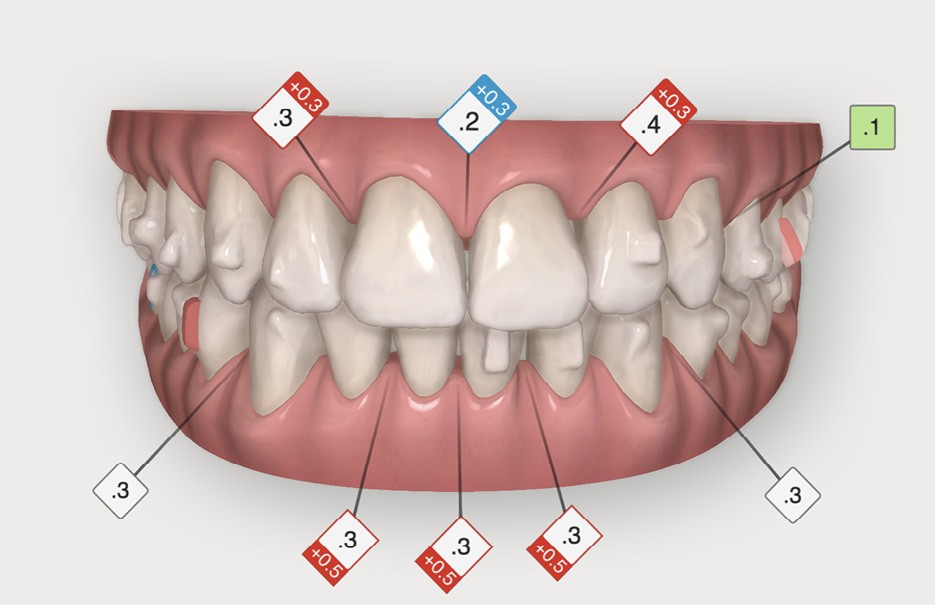

Après avoir traité les troubles transversaux et antéro-postérieurs, l’action orthodontique s’est concentrée sur les défauts d’alignement, grâce à des gouttières orthodontiques (fig. 4). L’avantage des gouttières par rapport aux dispositifs multi-attaches vestibulaires, c’est que l’alignement se fait avec une avancée moindre des bords libres des incisives et qu’elles permettent de définir plus précisément où l’on peut stripper pour gagner de la place et réduire les triangles noirs. En outre, le nettoyage des dents est facilité, ce qui est intéressant chez les patients ayant des atteintes parodontales.